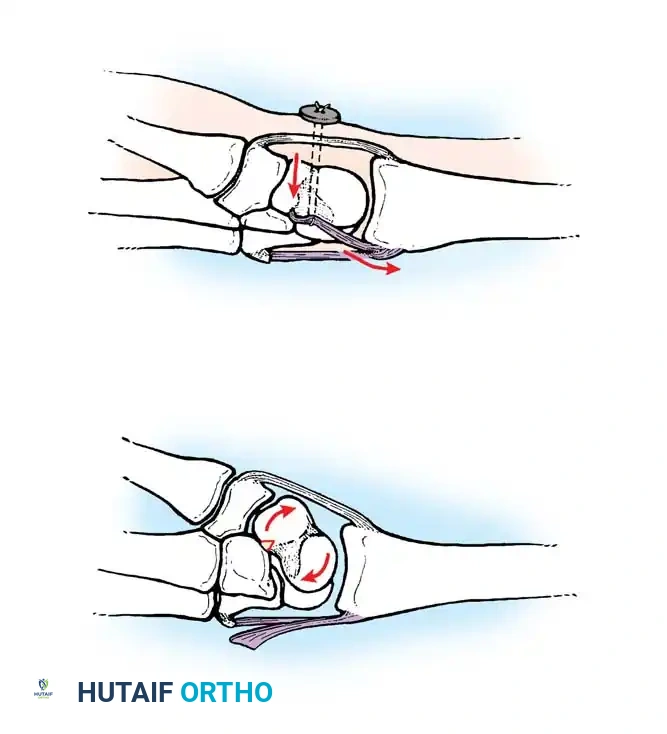

- Stage I (Scapholunate Failure): Disruption of the scapholunate interosseous ligament and volar radioscaphocapitate ligament.

- Stage II (Capitolunate Failure): The force propagates distally, disrupting the space of Poirier (palmar capitolunate joint), allowing the capitate to subluxate dorsally.

- Stage III (Triquetrolunate Failure): Disruption of the lunotriquetral interosseous ligament. The entire carpus separates from the lunate, resulting in a dorsal perilunate dislocation.

- Stage IV (Lunate Dislocation): The dorsal radiocarpal ligament fails. The capitate is driven proximally, forcing the lunate to extrude anteriorly into the carpal tunnel.